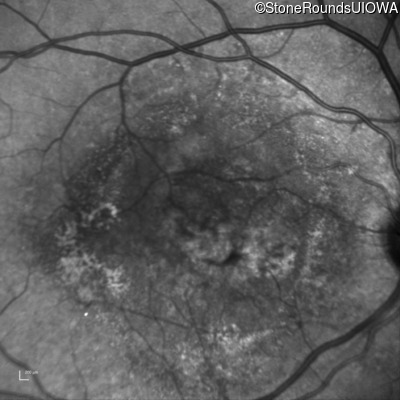

AR Stargardt Disease (IIA)

Age at visit: 59 years (Visit 3)

This 59 year old woman first noticed vision loss in her right eye a few months earlier. She has a cousin with Rhodopsin-associated RP.

Diagnosis & molecular findings

Disease Gene Allele 1 variant(s) Allele 2 variant(s) Inheritance mode

AR Stargardt Disease ABCA4 Arg219Thr AGA>ACA Gly863Ala (G)GA>(G)CA AR